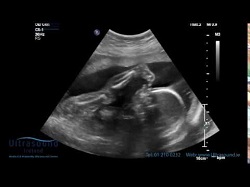

গর্ভাবস্থায় ফান্ডাল প্ল্যাসেন্টা: একটি নিরাপদ ও সাধারণ অবস্থান

পোস্টেরিয়র প্লাসেন্টা: গর্ভাবস্থায় সাধারণ ও নিরাপদ অবস্থান